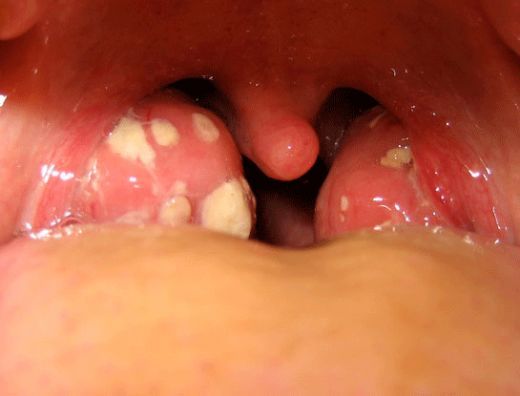

Geçmeyen Boğaz Enfeksiyonu Belirtileri ve Tedavisi

Hamilelikte Boğaz Enfeksiyonu Belirtileri ve Tedavisi